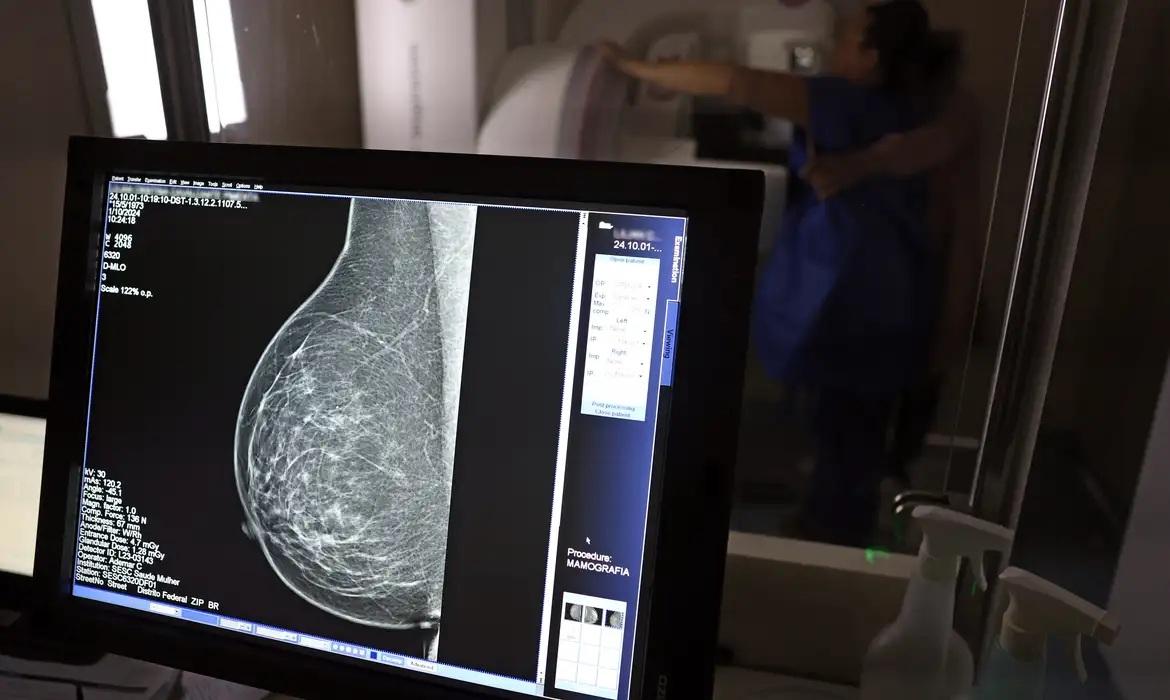

Ministério da Saúde passa a recomendar mamografia a partir dos 40 anosFoto: José Cruz/Agência Brasil

O Ministério da Saúde passou a recomendar o acesso a mamografia, via Sistema Único de Saúde (SUS), para mulheres de 40 a 49 anos – mesmo que não haja sinais ou sintomas de câncer de mama. De acordo com a pasta, a faixa etária concentra 23% dos casos da doença, e a detecção precoce aumenta as chances de cura.

Até então, a orientação era que o exame fosse feito a partir dos 50 anos.